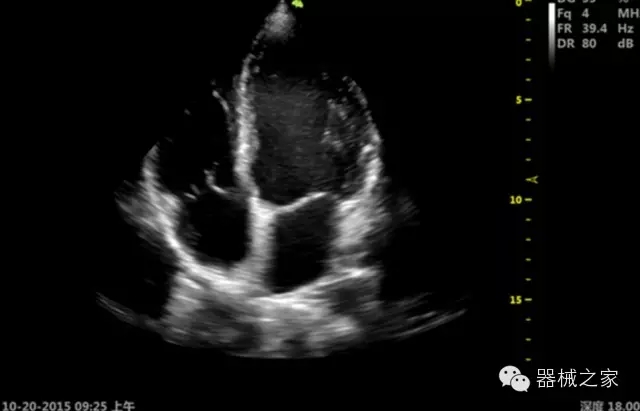

·心功能綜合指數(shù)(TEI指數(shù)):用于左、右心室整體心臟收縮舒張功能評(píng)估的測(cè)量方法;

·全方位可調(diào)M型:有利于更好的觀察心腔大小及室壁階段性運(yùn)動(dòng)的異常情況;

·組織多普勒成像(TDI):TDI可定量評(píng)價(jià)心肌運(yùn)動(dòng),判斷是否有局部病變,還可評(píng)價(jià)早期的舒張功能;

·MPTEE:經(jīng)食道探頭術(shù)中監(jiān)測(cè),可測(cè)量心臟前負(fù)荷(左室舒張末期大小、右房大?。⑿呐叛?、后負(fù)荷、收縮功能、室壁運(yùn)動(dòng)分析、肝靜脈血流(與中心靜脈壓相關(guān))等,術(shù)后還能及時(shí)評(píng)估手術(shù)效果評(píng)估;